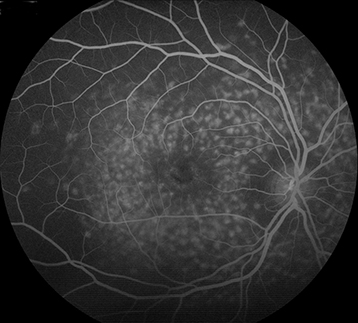

(See Figures 11.30.1 to 11.30.3.)

Yellow or yellow-white, fleck-like deposits at the level of the RPE, often in a pisciform (fish-tail) configuration.

Atrophic macular degeneration: May have a bulls eye appearance as a result of atrophy of the RPE around a normal central core of RPE, a beaten-metal appearance, pigment clumping, or marked GA.

Vermilion or light-brown fundus with obscuration of choroidal vasculature. Atrophy of the RPE just outside of the macula or in the midperipheral fundus, normal peripheral visual fields in most cases, and rarely an accompanying cone or rod dystrophy. Peripapillary sparing best seen by FAF. The ERG is typically normal in the early stages but may become abnormal late in the disease. The EOG can be subnormal.

IVFA often shows blockage of choroidal fluorescence producing a silent choroid or midnight fundus as a result of increased lipofuscin in RPE cells.

FAF can be helpful in diagnosis and in monitoring disease progression.